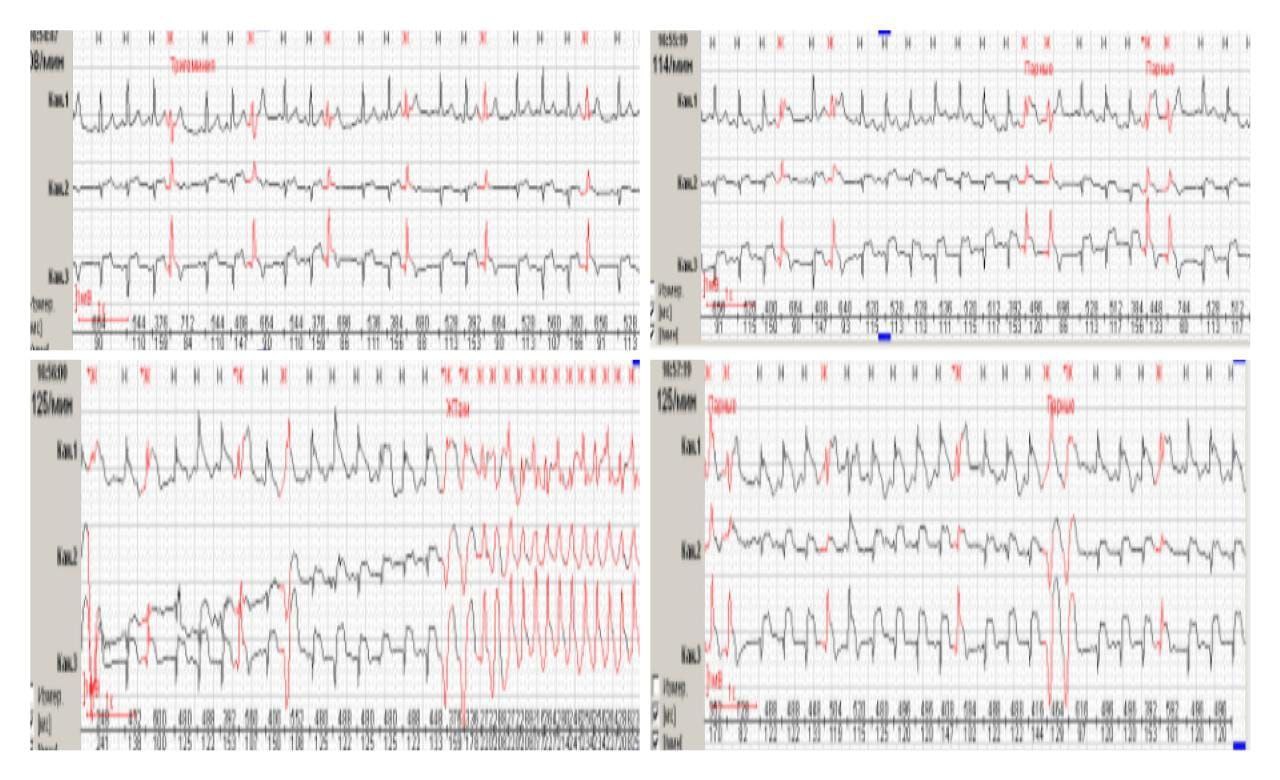

На ЭКГ

Анонимный опрос

21%

фибрилляция предсердий

18%

синусовый ритм с экстрасистолами

19%

НЖТ

27%

тахикардия с узкими комплексами на фоне ВПВ

14%

поломка аппарата

Проголосовало: 433